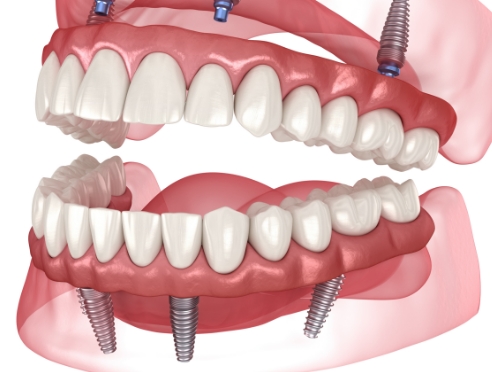

임플란트는 정확한 진단과 계획을 기반으로

여러 단계를 거쳐 진행되는 치료입니다.

환자분의 구강 상태에 맞춰

단계별로 안전하게 진행됩니다.

환자 상태에 맞는 개인 맞춤

임플란트 디자인을 적용합니다.